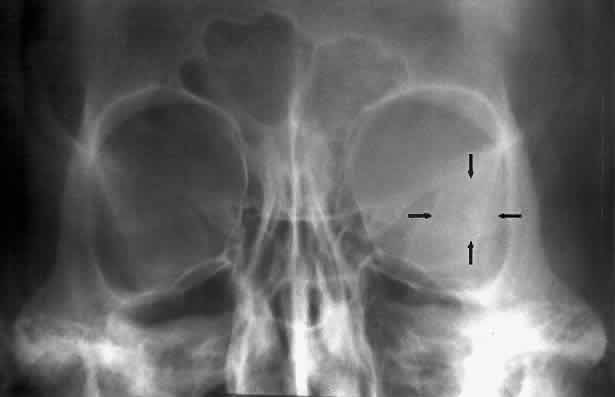

The posterior segment of the lateral wall courses posterior medially and can be seen in anterior projections such as the Caldwell view. This view allows direct visualization of the greater sphenoid wing contribution to the lateral wall. Bone density changes in the greater wing of the sphenoid, such as from a meningioma, can be detected. Fractures of the lateral orbital wall can occur from blunt trauma to the malar prominence. The zygomatic complex fracture (tripod) results from separation of the zygomatic-frontal, zygomatic-temporal, and the zygomatic-maxillary sutures. These fractures are associated with an inferior displacement of the malar prominence and a rounded lateral canthus (Figs. 8 and 9).

Fig. 8. A zygomatic complex fracture (tripod) after blunt trauma to the right cheek. Note the right zygoma is inferiorly displaced. (a, zygomatic-frontal suture separation; b, orbital rim disruption; c, opacification of maxillary sinus)